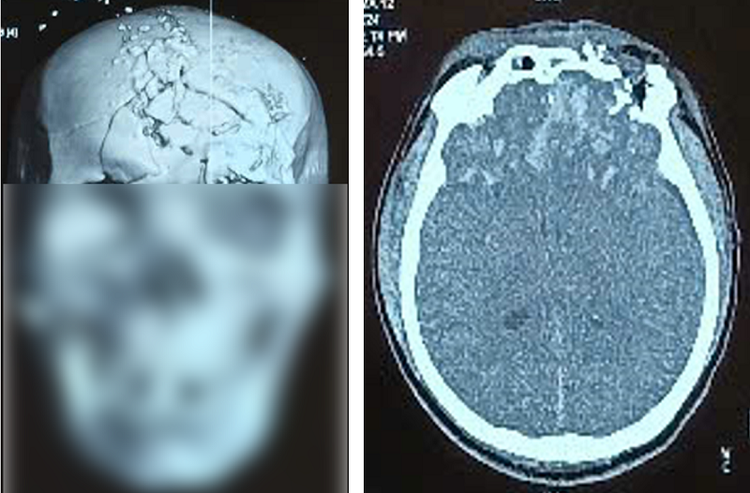

| Hình ảnh phim Cắt lớp vi tính xương sọ và tổn thương não khi bệnh nhân nhập viện - Ảnh: BVCC |

Bệnh nhân được chẩn đoán hôn mê, chấn thương sọ não hở: dập não vùng trán hai bên, vỡ xương vùng trán hai bên - đỉnh phải, vỡ xương phức tạp vùng hàm mặt, vỡ xương đá phải, bỏng độ II -III vùng mặt, bỏng độ II hai mắt. Bệnh nhân đã được phẫu thuật cấp cứu mở xương sọ vùng trán hai bên giải ép não, lấy dị vật, khâu vết thương phần mềm.